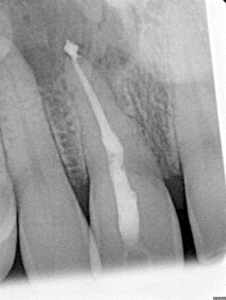

Root Canal / Retreatment

Clinical Cases